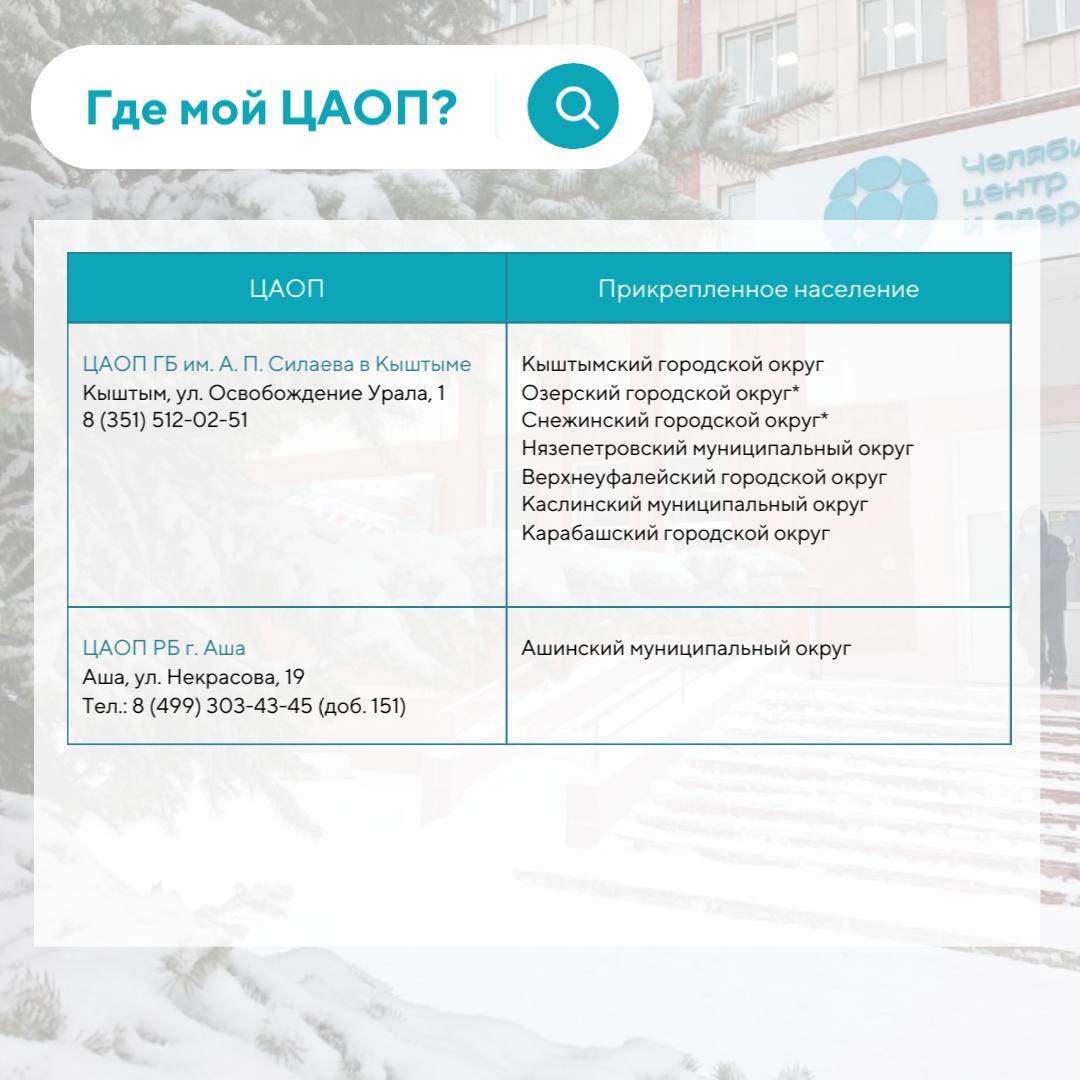

В Челябинской области пациенты прикреплены к конкретным Центрам амбулаторной онкологической помощи, а найти свой можно в карточках:

В Челябинской области пациенты прикреплены к конкретным Центрам амбулаторной онкологической помощи, а найти свой можно в карточках:

Инфографика предоставлена пресс-службой ЧОКЦОиЯМ

Инфографика предоставлена пресс-службой ЧОКЦОиЯМ